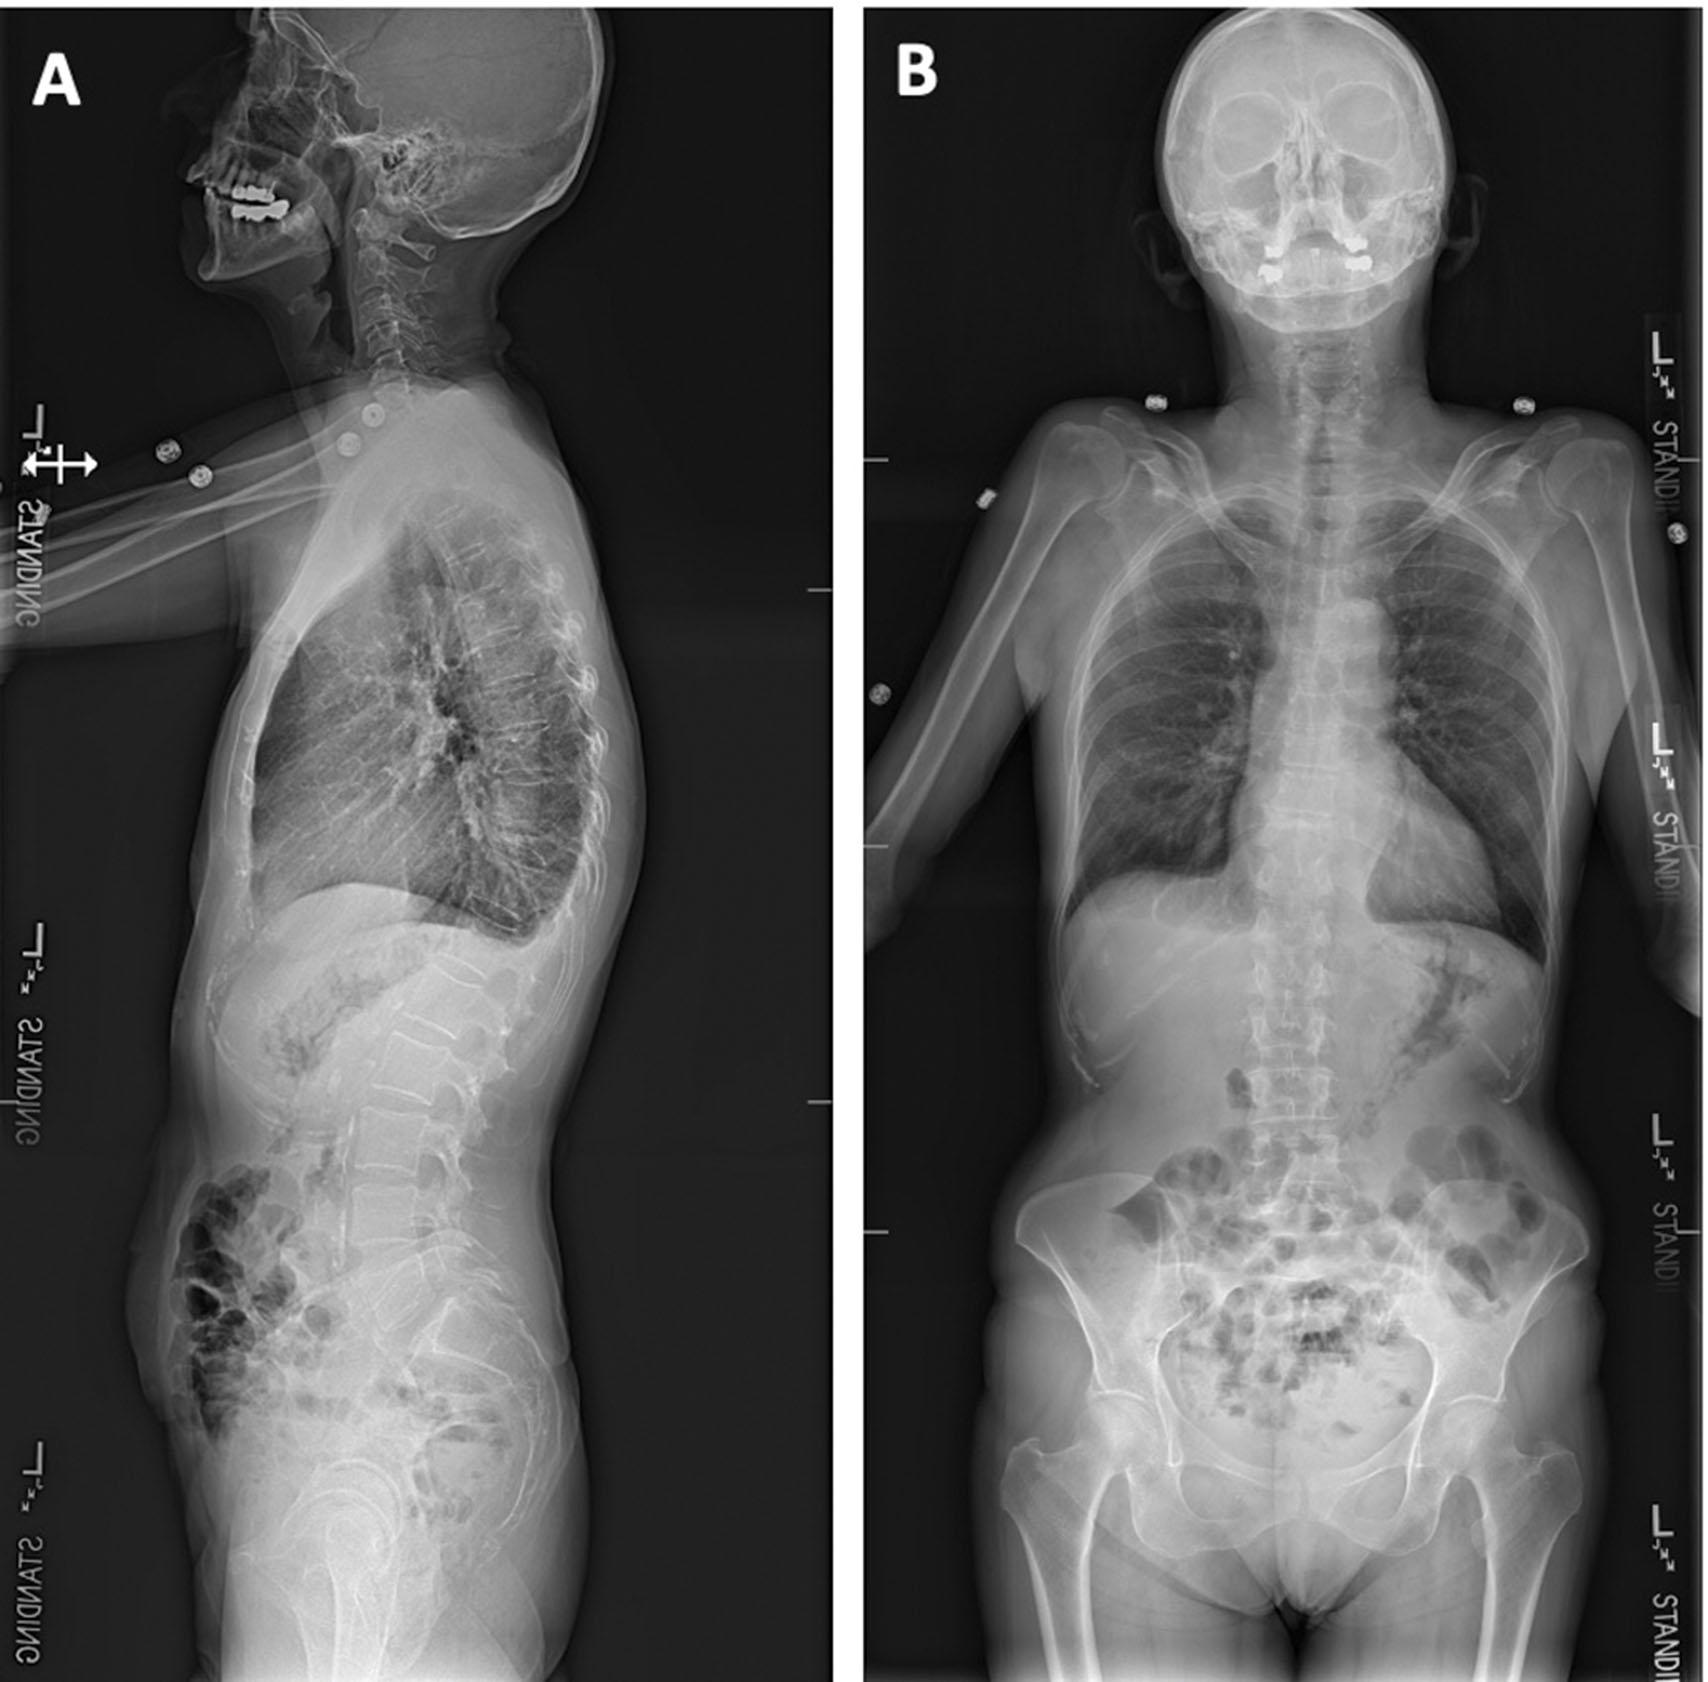

• History of present illness: A 62-year-old female with a history of seizures suffered a fall and presented with back pain. She was admitted for ongoing back pain, which was poorly controlled. The pain improved in the recumbent position and worsened with ambulation. She denies weakness or bowel/bladder dysfunction. She underwent imaging which revealed a compression fracture ( Figs. 24.1–24.3 ).

Fig. 24.3, Preoperative x-rays. (A) Anteroposterior (AP) and (B) lateral x-rays demonstrating a T10 compression fracture with focal kyphosis but no global imbalance present.